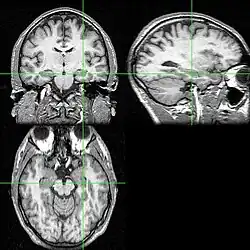

MRI scan of brain

An MRI scan with the hippocampus indicated in a coronal, lateral and horizontal view.